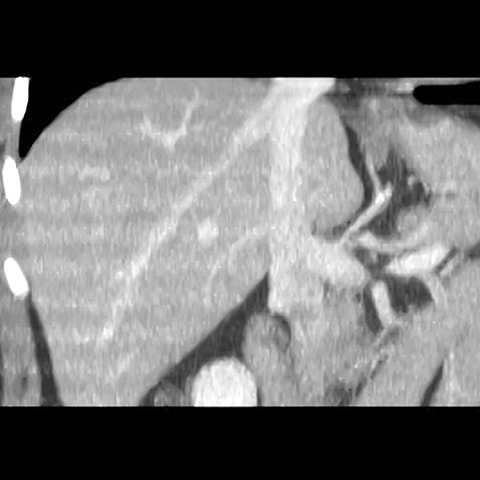

Normal Liver, CT ( coronal ) [3 of 5]